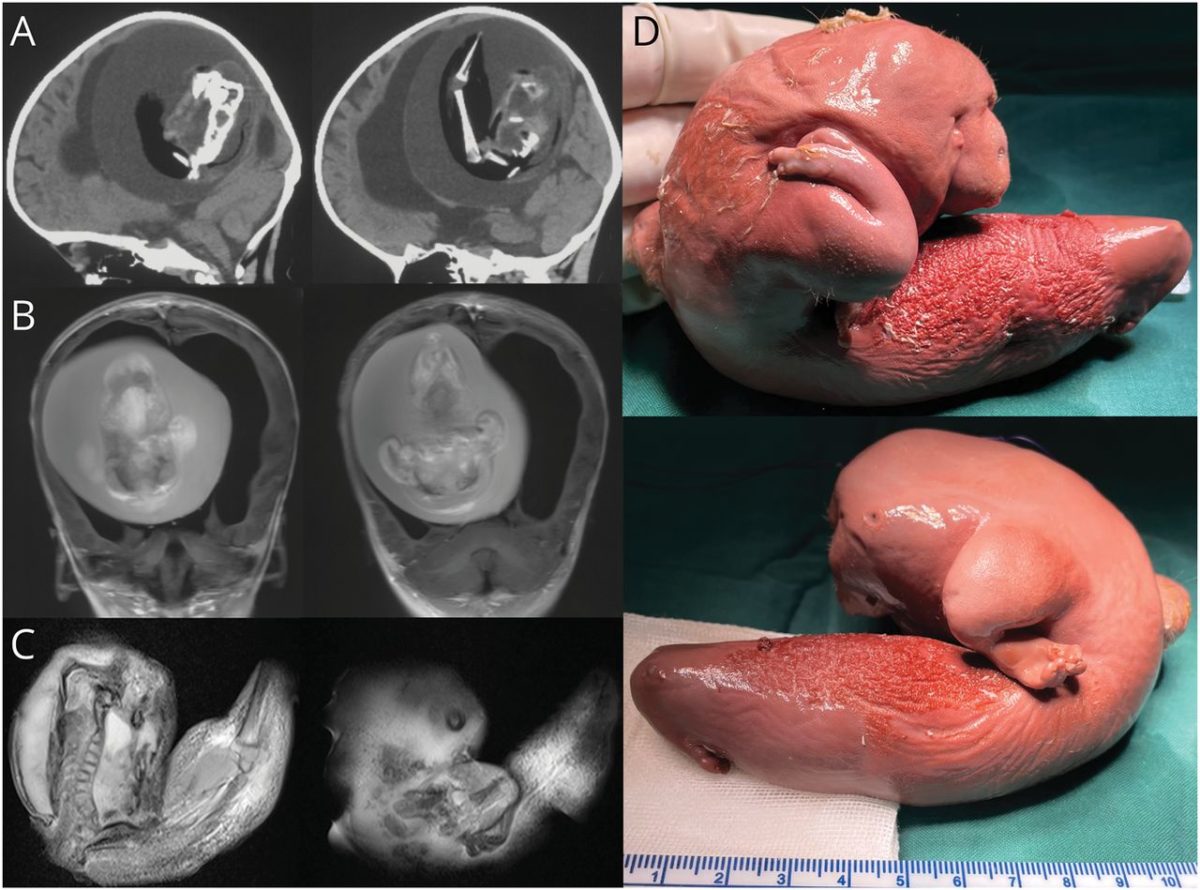

Η μικροσκοπική “εμβρυϊκή μάζα” φαίνεται να έχει αναπτύξει άνω άκρα και ακόμη και προεξοχές σαν δάχτυλα.

Οι γιατροί στο Πανεπιστήμιο Fudan στη Σαγκάη εξήγησαν ότι το παιδί παρουσίασε διευρυμένο κεφάλι και προβλήματα με τις κινητικές της δεξιότητες. Οι αξονικές τομογραφίες του κεφαλιού της έδειξαν ότι ο εγκέφαλός της ήταν συμπιεσμένος και ότι υπήρχε συσσώρευση υγρού που προκλήθηκε από μια σημαντικού μεγέθους μάζα.

Οι λεπτομέρειες στην σχετική δημοσίευση δεν είναι κατατοπιστικές, αλλά οι συγγραφείς περιγράφουν ότι πραγματοποιήθηκε χειρουργική αφαίρεση, που αποκάλυψε μια σπάνια περίπτωση “ενδοκοιλιακού εμβρύου μέσα σε έμβρυο”!

Με άλλα λόγια, το έμβρυο του αγέννητου διδύμου ήταν μέσα στο κρανίο της… αδελφής του.

Ωστόσο, υπήρξαν και άλλες παρόμοιες περιπτώσεις όπου τα παιδιά ανάρρωσαν καλά. Σε μια μελέτη, που δημοσιεύθηκε το 1982, επιστήμονες στο Νοσοκομείο του Λονδίνου ανέφεραν ένα έμβρυο μήκους 14 εκατοστών μέσα σε ένα παιδί ηλικίας 1,5 μήνα που παρουσίαζε μεγέθυνση του κεφαλιού. Το έμβρυο που αφαιρέθηκε είχε επίσης αξιοσημείωτα χαρακτηριστικά όπως αναπτυσσόμενα άκρα, κεφάλι και σώμα. Μετά το χειρουργείο, το παιδί λέγεται ότι είχε καλή ανάρρωση.